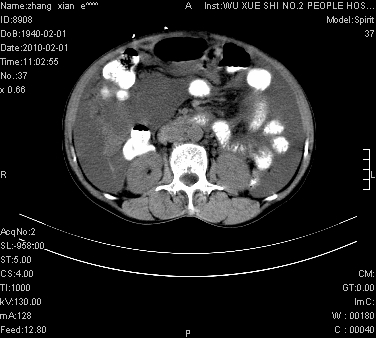

标题: CT24434:70岁 女 腹胀,腹水原因待查 [打印本页]

标题: CT24434:70岁 女 腹胀,腹水原因待查

腹盆腔大量积液,子宫增大,子宫颈增大外形不规则,内见低密度影,膀胱后壁显示不清,右腹股沟肿大淋巴结,脾脏囊性占位,子宫颈占位,子宫颈癌?建议增强。

考虑:1、腹膜转移,大量腹水;

2、脾占位性病变;

3、左侧卵巢占位性病变,建议增强进一步检查。

大量腹水,右肾、脾囊肿可能性大          考虑左侧附件区占位,建议增强